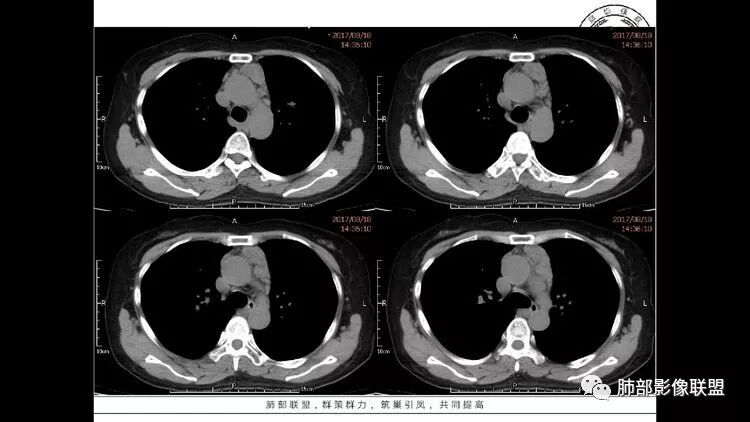

左肺下叶混杂密度病灶,其内可见空泡,周围ggo清楚,考虑浸润性腺癌。双肺散在多发薄壁囊腔和实性结节,以胸膜下及血管旁分布位于,气囊可见血管贴边征,双肺小叶间隔及中央间质增厚,局部可见磨玻璃影及树芽征,纵隔内淋巴结肿大,考虑LIP

综上,考虑左下肺浸润性腺癌+LIP

双肺多发大小不等囊腔,可见薄壁,部分囊腔内可见血管影,伴双肺多发结节,结合患者眼病及类风湿病史,考虑LIP可能大。另左肺下叶磨玻璃结节,边界清晰,内可见空泡,伴纵膈多发肿大淋巴结,不除外浸润性腺癌可能。

老年女性,长期使用激素史。双肺多发散在斑片状磨玻璃密度影及大小不等的薄壁含气囊腔,下肺相对较多较大。双肺多发结节,左肺上叶结节相对较大,界清,边缘光滑,分叶不明显。右肺下叶前外底段散在树丫。前上纵膈偏左侧不规则软组织团块,颗粒感,偏软。肺内囊腔及磨玻璃影考虑淋巴细胞间质性肺炎,或淋巴管肌瘤病。纵膈团块考虑淋巴管瘤。两者结合,考虑淋巴细胞增生病变。右肺下叶散在树丫,结核待排。双肺结节性质待定。

双肺多发散在斑片状磨玻璃密度影及大小不等的薄壁含气囊腔,下肺相对较多较大。双肺多发结节,界清,边缘光滑,分叶不明显。右肺下叶前外基底段散在斑片树芽。前上纵膈偏左侧不规则软组织团块,密度不均,其内可见不规则纤维样低密度,周围簇状小淋巴结。考虑1淋巴细胞间质性肺炎。2考虑纵膈胸腺淋巴瘤。

•镜检:在肺叶间隔、肺泡壁、支气管、细支气管和血管周围见块状混合细胞浸润,以成熟的淋巴细胞为主,有时可见生发中心,未见核分裂。此外尚有浆细胞、组织细胞、大单核细胞及少量嗜酸性细胞和巨噬细胞等。在伴发血红蛋白异常的病例,以浆细胞浸润为主。细支气管处浸润的淋巴细胞聚集可引起局部支气管狭窄和阻塞,导致典型阻塞性肺炎表现,但气腔未受到浸润细胞的累及。在病变较严重区域,常见闭塞性动脉内膜炎。肺间质有多量网状纤维组织增生,形成纤维化,最后进展为蜂窝状肺。极少数病例合并结节状肺淀粉样变。